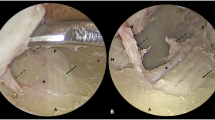

A cadaveric dissection study was performed of 15 embalmed human heads (30 orbits). Red and blue coloured silicone was injected into the bilateral common carotid arteries and internal jugular veins respectively. The frontal nerve was excised en bloc from the superior orbital rim back to the superior orbital fissure via an eyelid crease approach. The infraorbital nerve branch extending from the infraorbital foramen back to the maxillary nerve at the foramen rotundum was excised, as previously described [2]. Following the nerves’ en bloc excision, the maximum transverse diameter of the frontal and infraorbital nerves within the orbit, and the maxillary nerve within the pterygopalatine fossa were visualised and measured. All measurements were recorded using a ruler with 1 mm increments and therefore a precision of 0.5 mm. The mean and standard deviation values were derived from these measurements, and the values represented to 2 decimal points. Ethics approval was provided by the institutional review board.